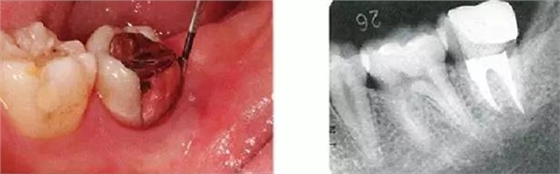

右下4牙冠牙根破折案例。照片是破折前4個(gè)月拍攝的。牙周袋深度為3mm以下,牙周組織為正常狀態(tài)(右下5是以前由智齒矮小齒移植而來(lái))。破折后,舌側(cè)咬頭破折至傾斜的牙根處,破折片與牙齦相連。

去除破折片進(jìn)行了修復(fù)治療。3年后,上頜腭側(cè)有6mm、近中有4mm的牙周袋。X片可觀察到嚴(yán)重的骨吸收現(xiàn)象??赏茢喑鍪瞧普垡鸬母街鴨适?。